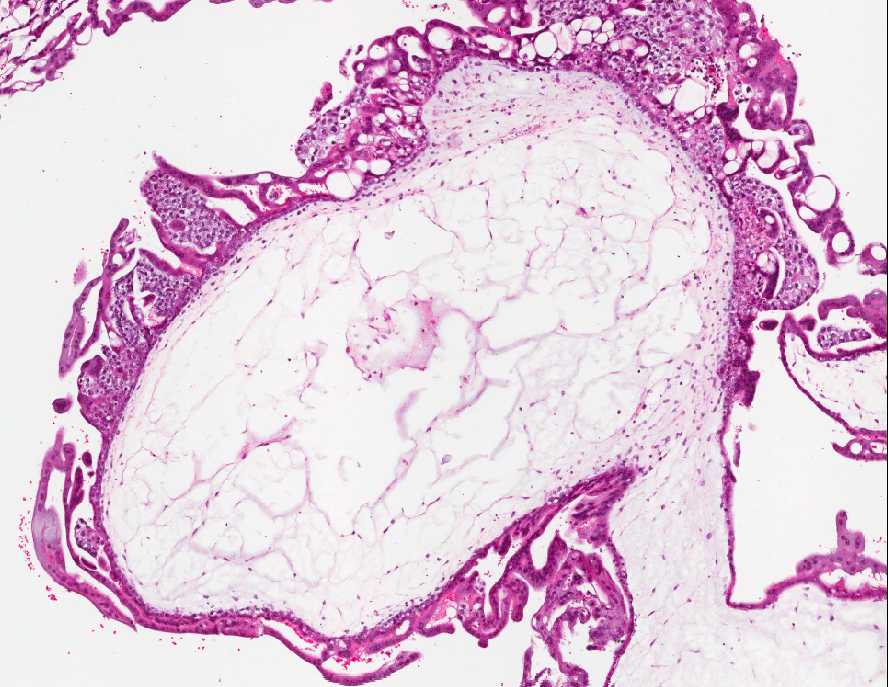

Man erkennt unregelmäßig verzweigte, und deutlich vergrößerte, vielfach ödematös aufgetriebene Zotten. Der Trophoblast mit zirkulärer, medusaartiger Hyperplasie des Synzytiotrophoblasten und intermediären Trophoblasten. Miterfasst dezidualisiertes Endometrium.

Abb. 316: Chorionzotten mit moliger Degeneration und atypischem, medusaartig proliferiertem und biphasich differenzierter Trophoblast